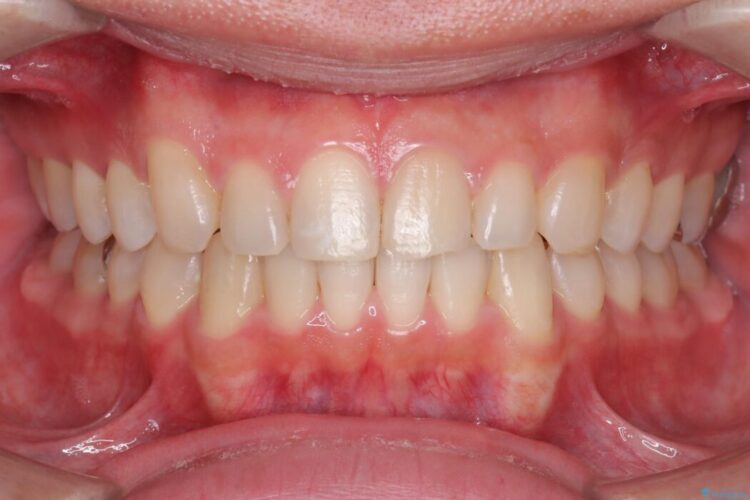

歯の隙間とデコボコ、シザーズバイトも改善され、咬み合わせや見た目が整い、患者様にも大変ご満足いただけました。